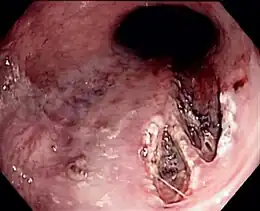

| Laceração de Mallory-Weiss afetando o lado do esôfago da junção gastroesofágica | |

A síndrome de Mallory-Weiss ou Síndrome da laceração gastroesofágica refere-se ao sangramento proveniente de lacerações das paredes na junção do estômago com o esôfago induzidos por ataques de tosse ou vômito.

O diagnóstico definitivo é feito por endoscopia. Medir a pressão arterial e frequência cardíaca ajudam a manejar a gravidade da hemorragia.[2]